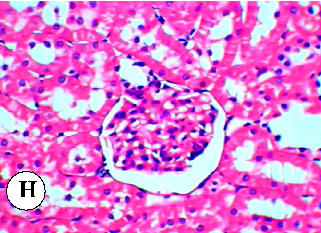

Figure 21

Figure 21 Chart

Summary comparison of nephroprotective efficacy across the different plant oils evaluated against diazinon-induced renal damage.

Protective effect of some plant oils on diazinon induced hepatorenal toxicity in …